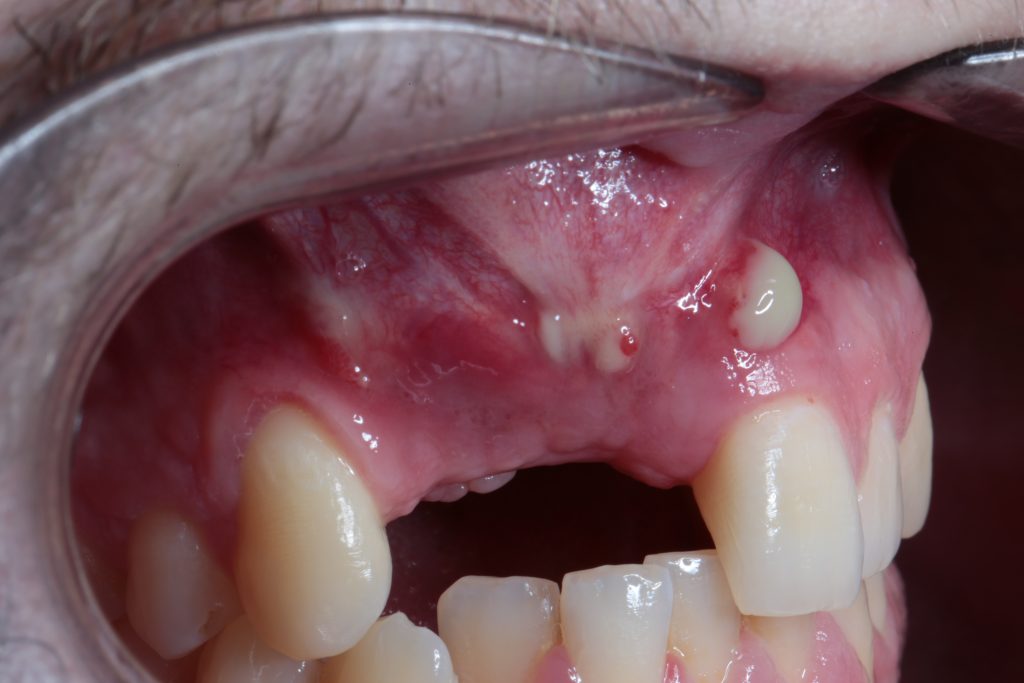

#2. The Rotated Palatal Flap Technique

We can prevent our graft from exposure by doing a two-layer-closure. We can use a rotated palatal flap of connective tissue to act as a first layer and then suture the mucosa over it.

If wound dehiscence of the first mucosal layer may happen, we still having the chance that our rotated palatal flap; we have to keep in mind that it keeps its vascularization, will cover and prevent our graft from exposing to the oral cavity.